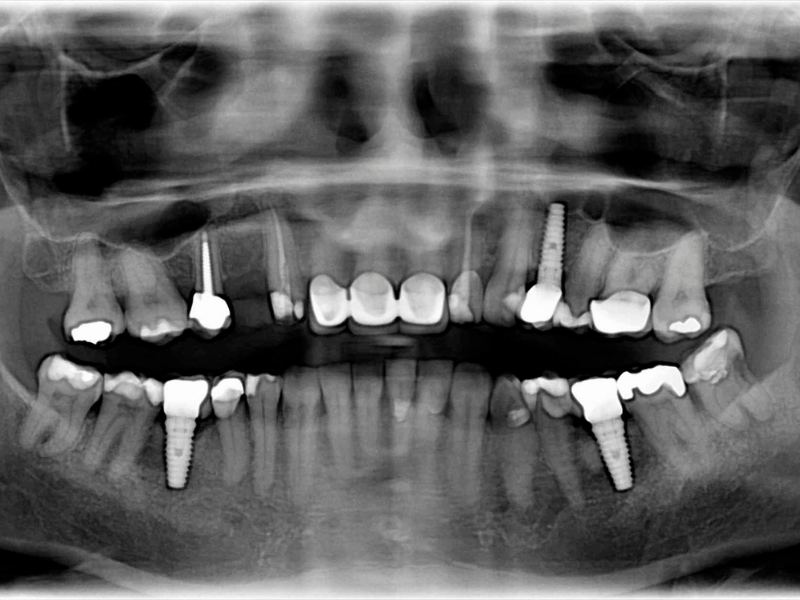

At Plaza Dental Specialty Group in Gardena, we specialize in restoring smiles with affordable, long-lasting dental implants. Whether you're missing one tooth or several, implants offer a permanent tooth replacement that looks and feels natural. Serving Gardena, Los Angeles, Torrance, and nearby areas, we’re here to help you smile, eat, and live with confidence again.

Perfect for replacing one missing tooth, our single dental implants in Gardena restore full function and blend seamlessly with your natural smile—without affecting surrounding teeth.

For multiple missing teeth, implant-supported bridges offer a stable, long-term alternative to traditional bridges. We anchor them securely using dental implants for added strength and durability.

Need to replace an entire row of teeth? Our full arch dental implants near Los Angeles, including All-on-4® options, provide a secure, natural-looking solution with fewer implants and faster results.